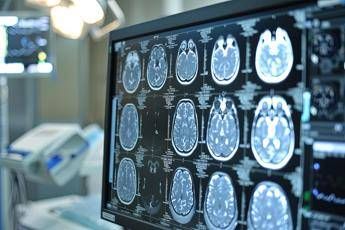

Neoplasie cerebrali, in Italia ogni anno 3mila casi di glioma

(Adnkronos) – Una volta erano considerate delle neoplasie rare, ma oggi i gliomi sono sempre più diffusi. In Italia i casi annui ammontano a oltre 3mila e corrispondono al 40% di tutti i tumori cerebrali primitivi. Tra i gliomi, quelli di basso grado di frequenza più rara rappresentano una sfida clinica rilevante anche per la loro evoluzione e l'assenza di trattamenti mirati, oltre alla resistenza che dimostrano ai trattamenti convenzionali. Sono malattie orfane di cui si parla poco anche fra i clinici, tra le istituzioni e sui media. Perciò la Fondazione Aiom (Associazione italiana di oncologia medica) ha lanciato nei mesi scorsi 'I gliomi', una campagna nazionale online di formazione e informazione. Sono stati organizzati webinar rivolti agli oncologi medici e alle altre figure sanitarie coinvolte nel team multidisciplinare. Sono stati indirizzati a pazienti e caregiver ulteriori eventi online insieme a un'attività di sensibilizzazione sui principali social media. I risultati dell'iniziativa sono presentati oggi in una conferenza stampa virtuale promossa da Fondazione Aiom. Il progetto è stato realizzato con il contributo non condizionante del Gruppo Servier in Italia. "Sono tumori cerebrali molto complessi e che spesso vengono diagnosticati in età giovanile – afferma Saverio Cinieri, presidente di Fondazione Aiom – Si sviluppano da cellule del cervello chiamate gliali e possono avere una prognosi variabile, ma potenzialmente a lungo termine. La gestione della patologia richiede una stretta collaborazione fra neurochirurgo, radioterapista e oncologo medico. Attraverso il bisturi è possibile rescindere la massa tumorale oppure eseguire una biopsia grazie a nuove e sofisticate tecnologie. La radioterapia permette di ridurre il rischio di recidiva o eliminare quella parte di cancro che non è stato possibile rimuovere chirurgicamente. Viene somministrata insieme alla chemioterapia e le sedute sono di solito diluite nel corso del tempo, per limitare l'impatto degli effetti collaterali. Infine, l'oncologo medico deve scegliere i farmaci da somministrare e deve selezionarli valutando le condizioni cliniche del singolo paziente". "Anche per il trattamento dei gliomi, in particolare quelli di basso grado, si può ricorrere all'oncologia di precisione che potrà ridisegnare la pratica clinica nel prossimo futuro – illustra Enrico Franceschi, direttore dell'Oncologia del sistema nervoso all'Irccs Istituto delle scienze neurologiche di Bologna – E' molto importante verificare la presenza o meno delle mutazioni Idh1 e Idh2. Questi biomarcatori indicano specifiche patologie caratterizzate da una prognosi decisamente più favorevole e maggiore sensibilità dei gliomi alla radio e chemioterapia. Al momento della diagnosi è quindi essenziale l'esecuzione precoce di alcuni test molecolari per identificare al meglio i diversi sottotipi di gliomi. Tra le terapie di nuova generazione vi è anche vorasidenib, un farmaco orale inibitore Idh1 e Idh2 che ha dimostrato di essere un trattamento efficace nel posticipare la radio e chemioterapia nei gliomi di basso grado ed è una rilevante innovazione medico-scientifica". "Come tutti i tumori cerebrali – prosegue Cinieri – anche i gliomi di basso grado hanno un forte impatto sulla vita del paziente. Sono tante le complicanze che possono verificarsi durante l'intero percorso di cura, perché intervenire sul cervello umano con radiazioni ionizzanti o con interventi chirurgici può comprometterne alcune funzioni basilari. Tra queste vi sono le capacità di parlare o di movimento. Si rendono a volte necessari interventi riabilitativi di logopedisti, fisioterapisti o altri professionisti come lo psiconcologo. Ricevere la notizia della presenza di un tumore in una zona così particolare e delicata porta quasi sempre a depressione e ansia, soprattutto quando il primo approccio è un periodo di osservazione privo di un trattamento attivo. Le terapie innovative sono in grado di prolungare in modo significativo la sopravvivenza libera da progressione e garantiscono un buon profilo di sicurezza e tollerabilità". "Ancora una volta l'oncologia medica è centrale nella gestione multidisciplinare di neoplasie estremamente complesse ed insidiose – sottolinea Franceschi – Il trattamento dei gliomi inizia nel momento della diagnosi che deve essere sia morfologica che molecolare. Esistono infatti 150 diversi sottotipi di neoplasia cerebrale ed è fondamentale riconoscere fin da subito le caratteristiche del singolo caso per poter così selezionare le terapie più appropriate. Fino a pochi anni fa avevamo a disposizione solo chirurgia, radioterapia e chemioterapia. Ora i farmaci ad azione mirata sono una realtà anche nella cura dei tumori cerebrali che esprimano specifiche alterazioni molecolari". "Nasce da questo rapido progresso nei trattamenti la nostra campagna d'informazione rivolta principalmente a specialisti clinici e pazienti – conclude Cinieri – L'oncologia medica è in costante evoluzione ed è compito di associazioni e fondazioni garantire sempre un aggiornamento scientifico qualificato. L'oncologia di precisione è una realtà consolidata in molte forme di cancro ed è un approccio che indirizza sempre più le nostre scelte terapeutiche. Sta portando a risultati davvero interessanti ed inimmaginabili fino a pochi anni fa anche per neoplasie rare e difficili da trattare come i gliomi di basso grado Idh mutati".